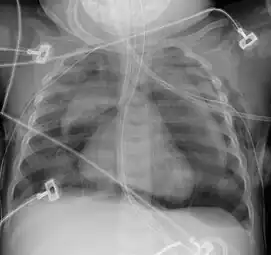

Pneumomediastinum and right sided pneumothorax post first rib fracture in a mountain biking accident. -